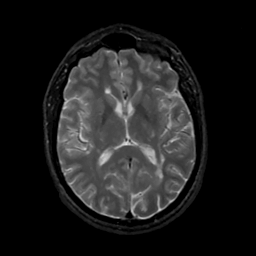

MR Study #15, June 9, 1991 -- Slice #27

[Home][Help][Clinical][Tour 1][Tour 2] Slice 27